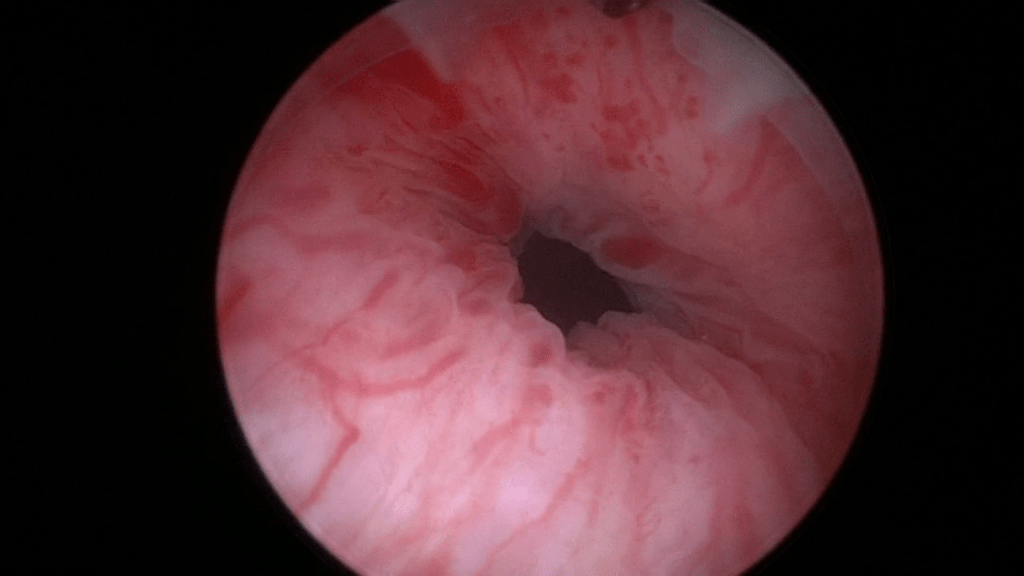

Lastly inject the final 0.5ml of Bulkamid® hydrogel at the 6 o’clock position.

Final image of the mid-urethra after creating four depots of Bulkamid® at the 12, 3, 9 and 6 o’clock positions.